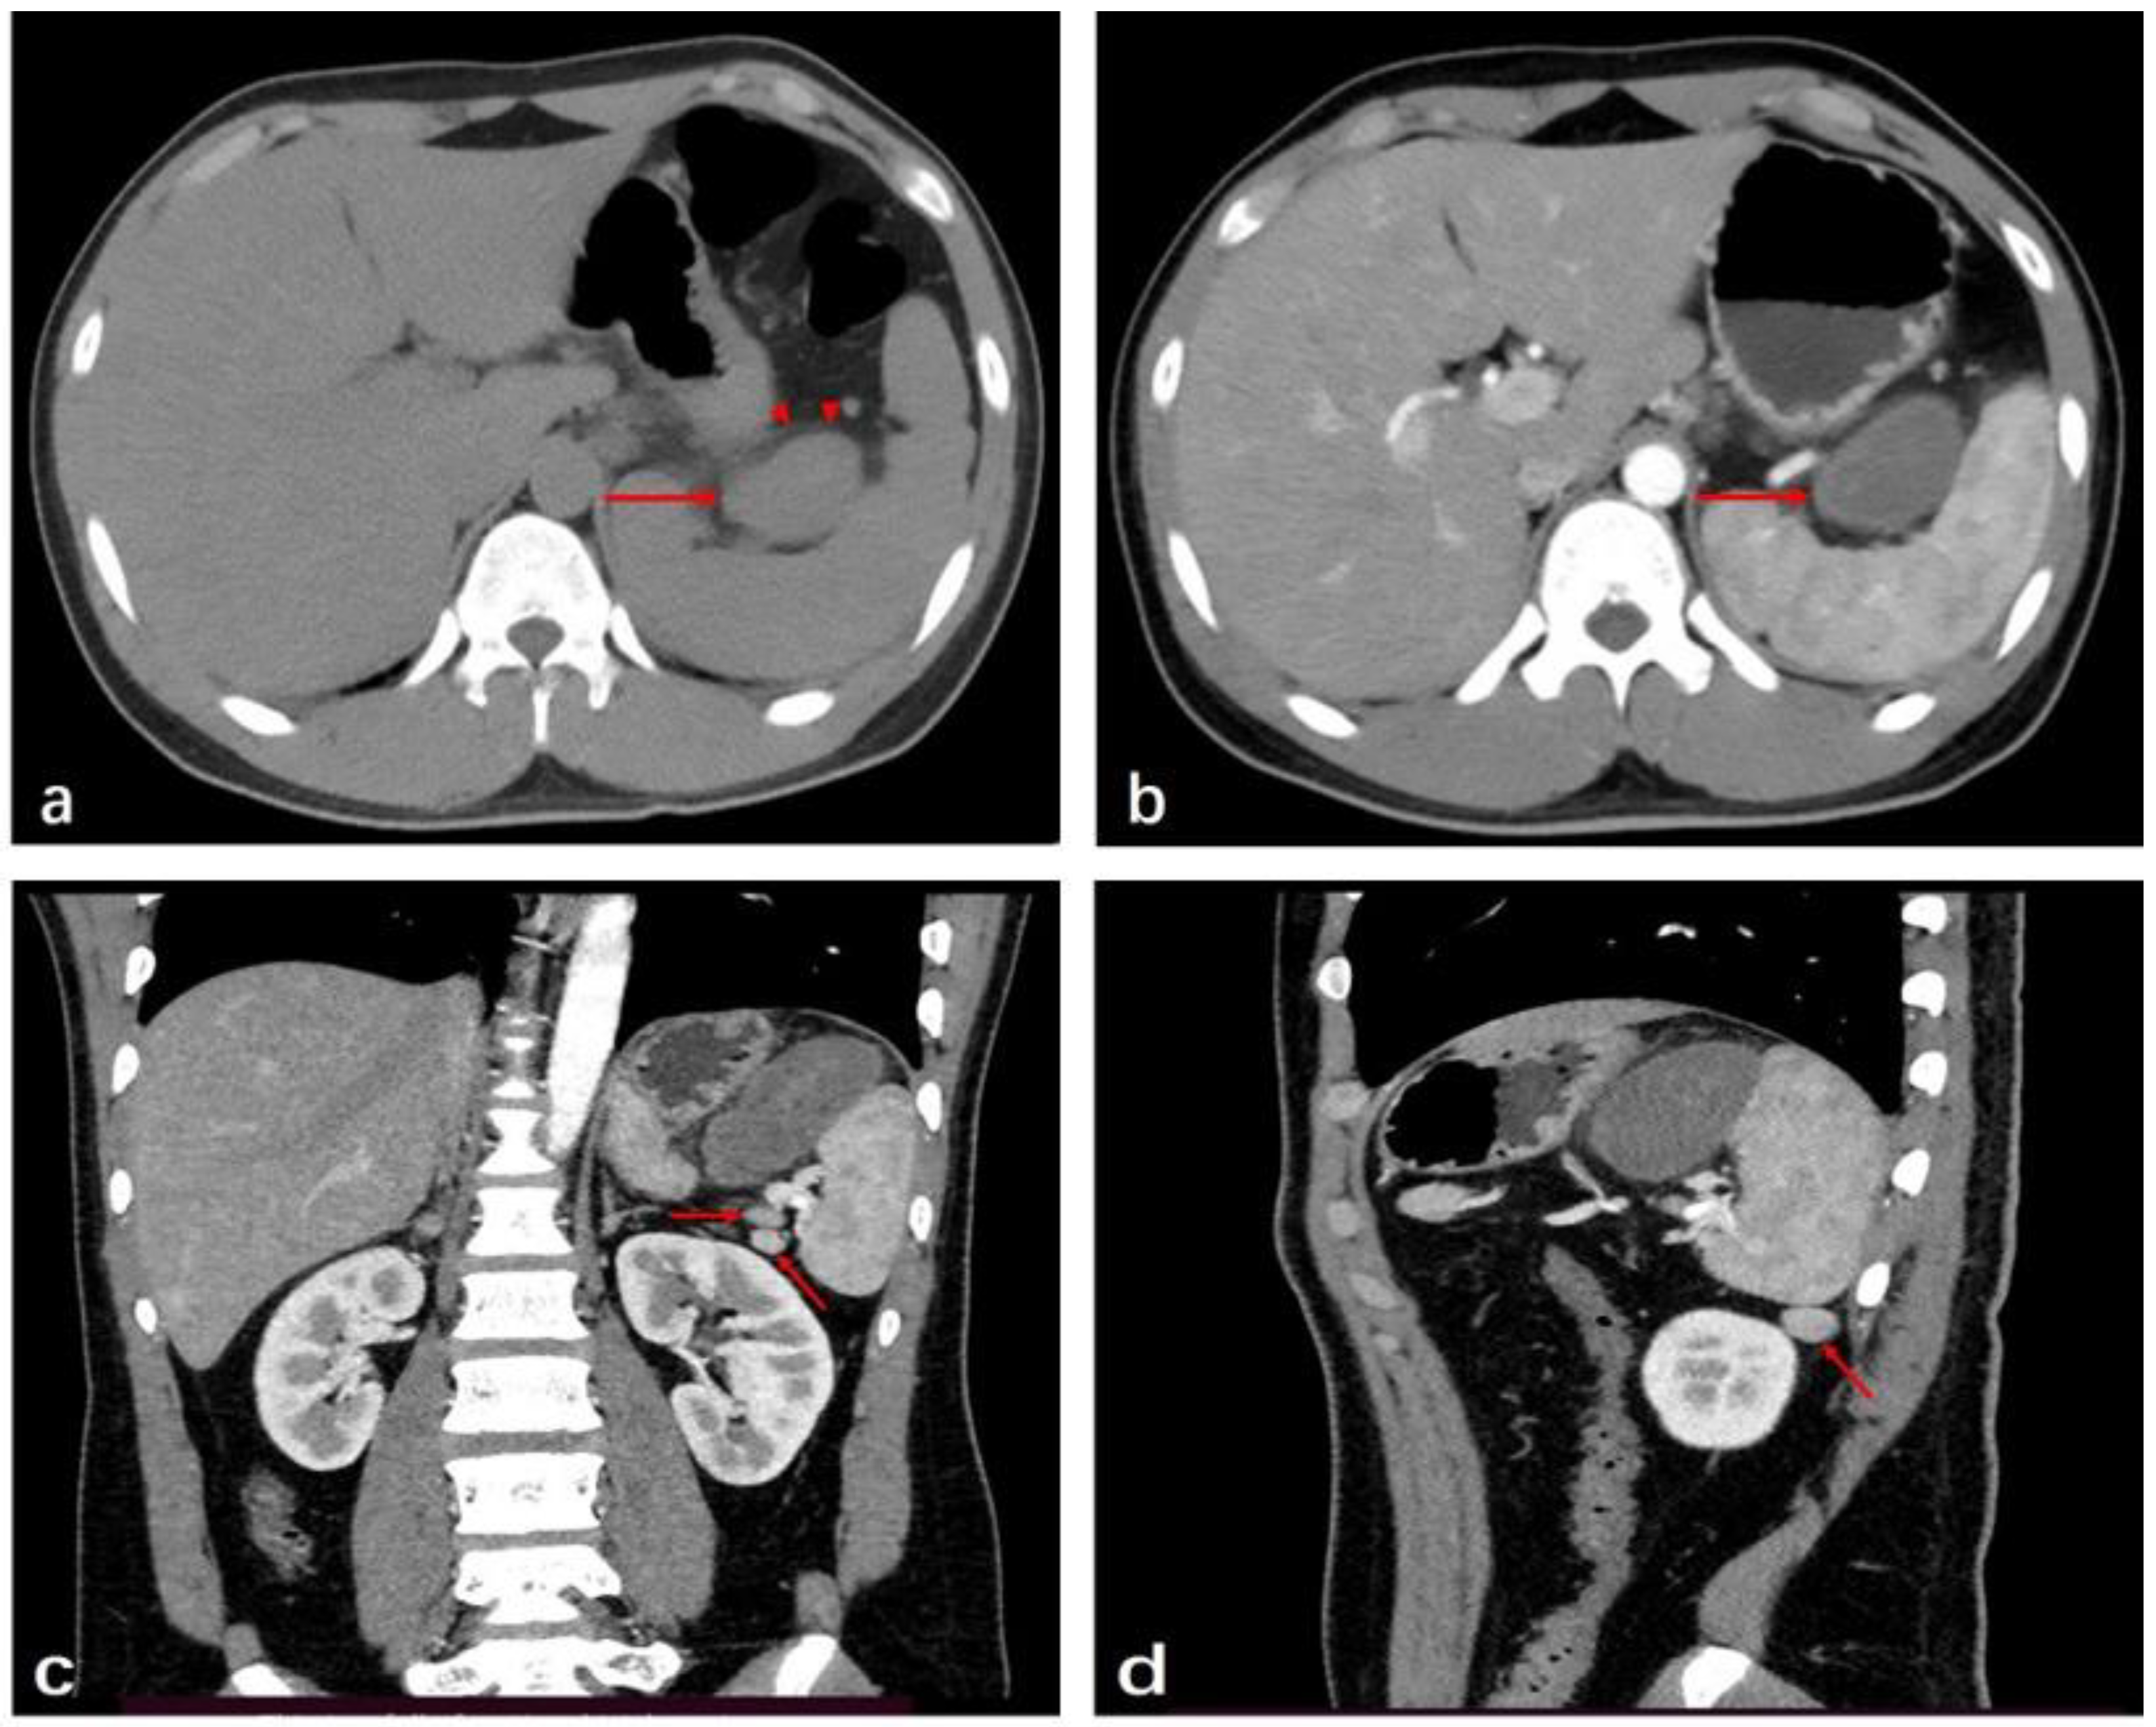

2. Case Presentation